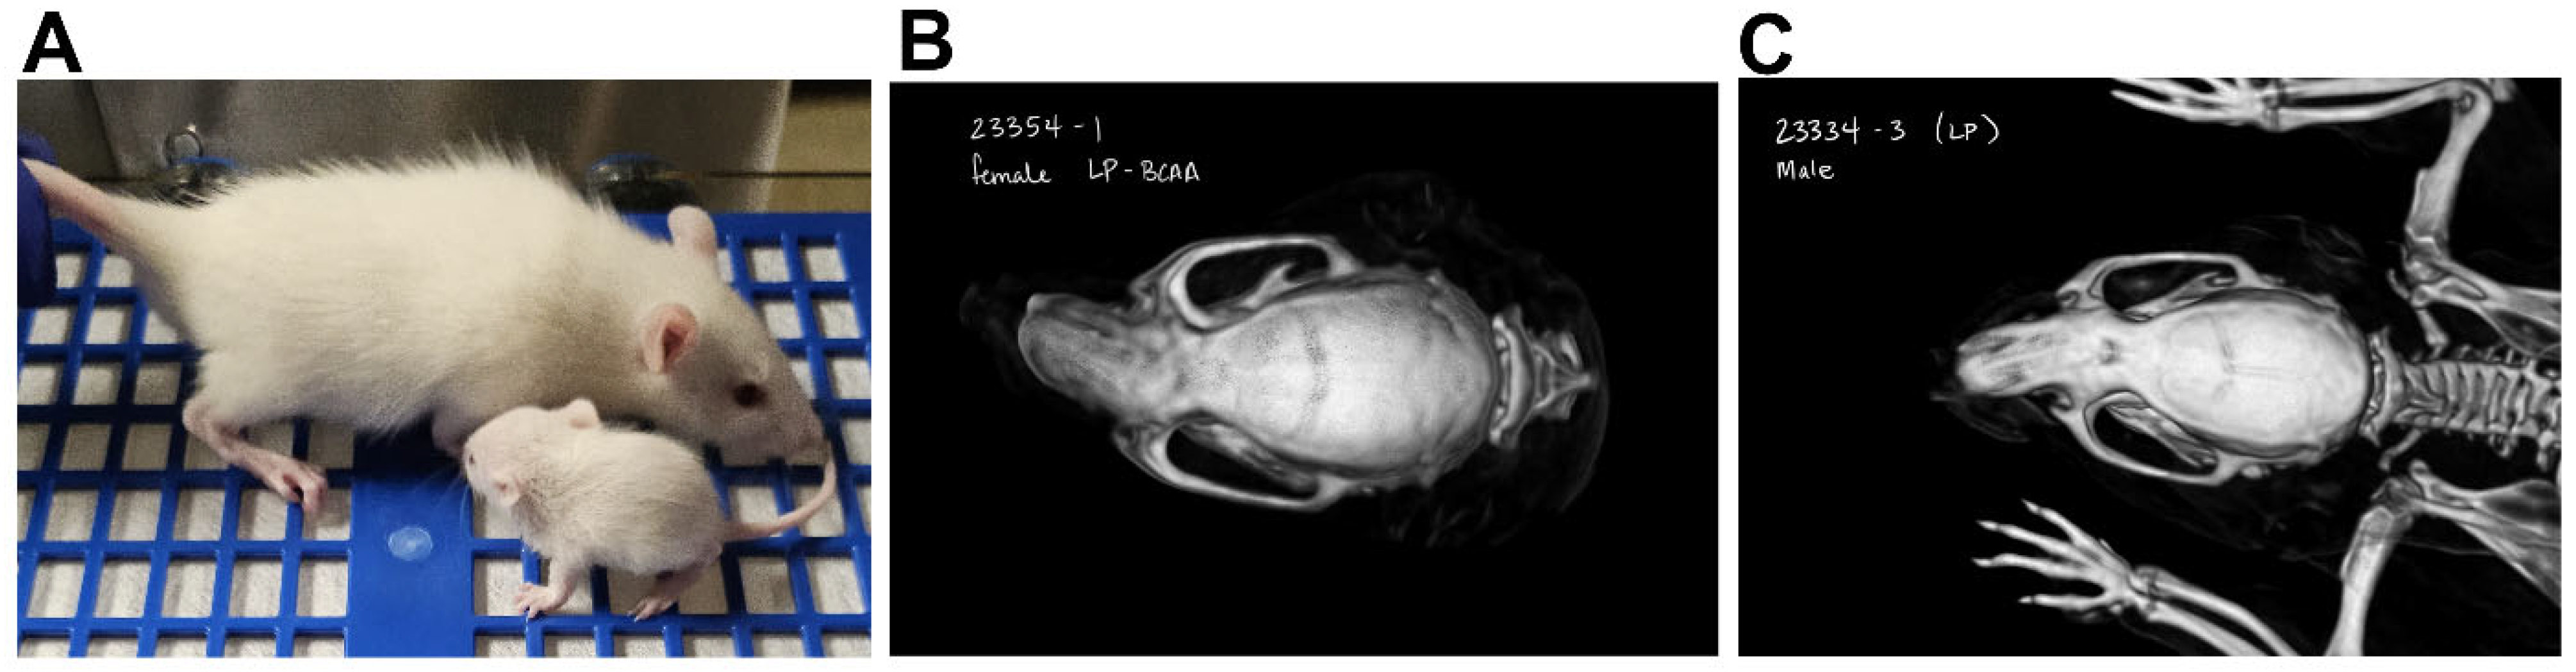

2.4. Computed Tomography Scan

3.4. Maternal Protein Restriction Affected Offspring Body Weight and Reduced Craniofacial Bone Dimensions